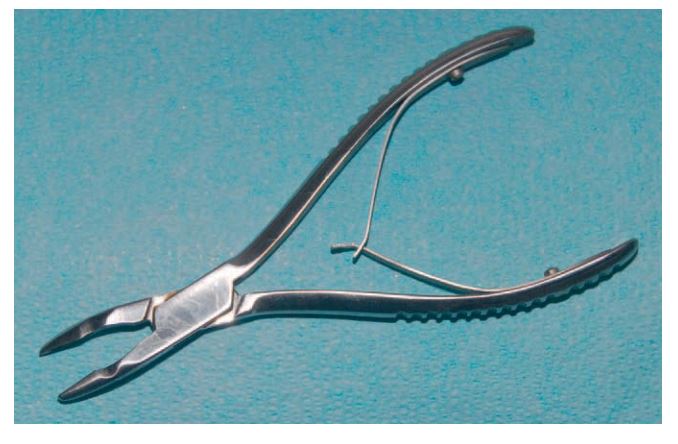

Kềm gặm xương (ronguer)

Kềm có mỏ bén, khép chặt lại khi tay bóp cán kềm. Trên cán kềm có thanh đàn hồi nên khi buông lỏng tay thì kềm sẽ mở ra. Đặc điểm này giúp các phẫu thuật viên dễ dàng lặp lại các động tác gặm xương mà không cần tốn sức để mở kềm ra sau khi bóp. Phần mỏ kềm có thiết kế lõm hướng về phía trong, có thể chứa 1 ít xương sau khi gặm.

Kềm gặm xương không được dùng để nhổ răng, vì mỏ kềm được thiết kế nhằm để cắt hơn là để ôm lấy răng, dùng sai sẽ gây mòn kềm.

Kềm gặm xương cũng khá là mắc tiền, nên chú ý cẩn thận khi sử dụng. 1 loại kềm gặm xương hay gặp khác là kềm Kerrison, chủ yếu được sử dụng trong nâng xoang cửa sổ (nâng xoang hở).